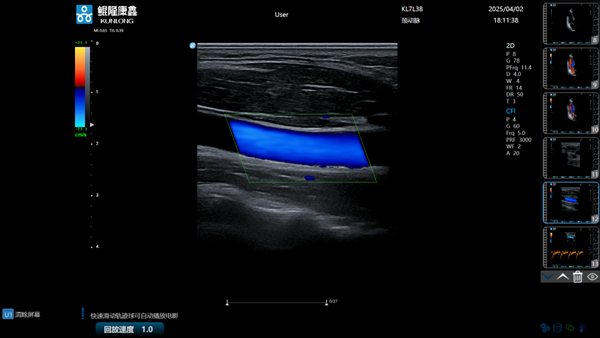

据悉,,,,,,,鲲隆康鑫自主研发的彩色多普勒超声诊断仪是一款集成了先进超声成像手艺的立异型医疗装备,,,,,,,该产品依附128通道数字波束形成手艺,,,,,,,实现黑点追踪、组织多普勒成像等多种高级成像功效,,,,,,,具有图像清晰、功效周全、操作便捷等特点,,,,,,,在要害手艺指标上已靠近国际主流水平,,,,,,,可用于腹部、心脏、血管、妇产等临床诊断,,,,,,,为临床医生提供更精准、更高效的诊断依据。。。。